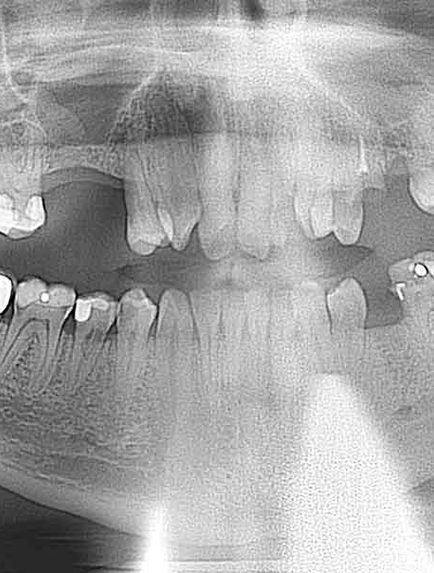

PROGRESS NOTES: 3 on 6 Consult- Pt. on time for apt. Took Pano Pt interested in 3 on 6 for U&L Dr. Roberts examined- Tx- U&L 3 on 6- Pt. has under bite & Dr. Roberts would like to bring the upper jaw forward & the lower jaw back. Nv: 3 on 6 impressions Assisted by Chelsea

Ext # 31, 30, 29, 28, 27, 26, 25, 24, 22, 21, 18, 14, 12, 11, 10, 9, 8, 7, 6, 5, 2 Implant/BG placement - Upper 3, 6, 7, 10, 11, 14 Lower 19, 21, 22, 26, 27, 30

extracted tooth number #31, 30, 29, 28, 27, 26, 25, 24, 22, 21, 18, 14, 12, 11, 10, 9, 8, 7, 6, 5, 2

pulled back tissue on #3, 6, 7, 10, 11, 14, 19, 21, 22, 26, 27, 30 expanded holes using Neodent replace tapered system Neodent

implants Reference #: 2x 140.629 2x 140.684 2x 140.690 1x 140.683 1x 140.688 1x 140.627 3.5x8mm ref-

140683-lot-8003271541 4.3x10 mm, ref-140-688-lot-8002391211 Healing abutment #: 2 mm